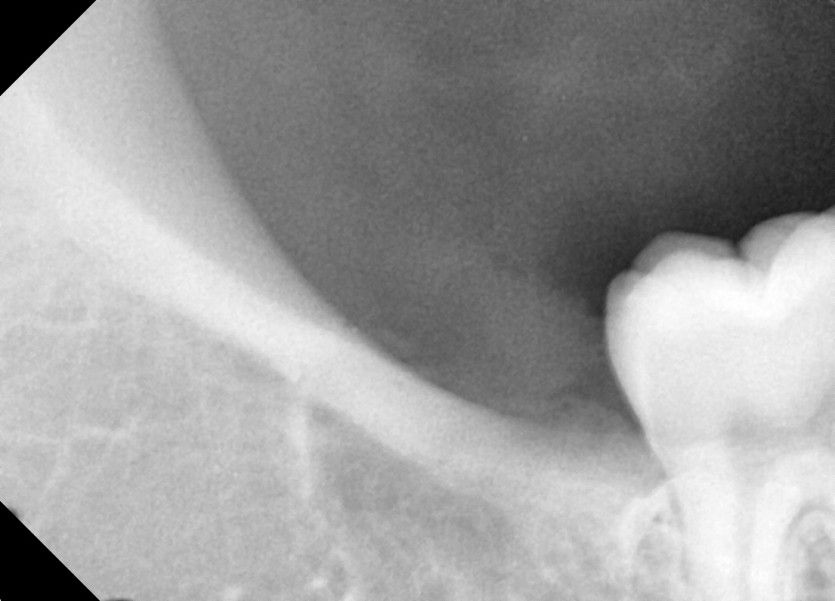

#18,48 사랑니 발치

구강외과 전문의가 당일 발치했습니다.